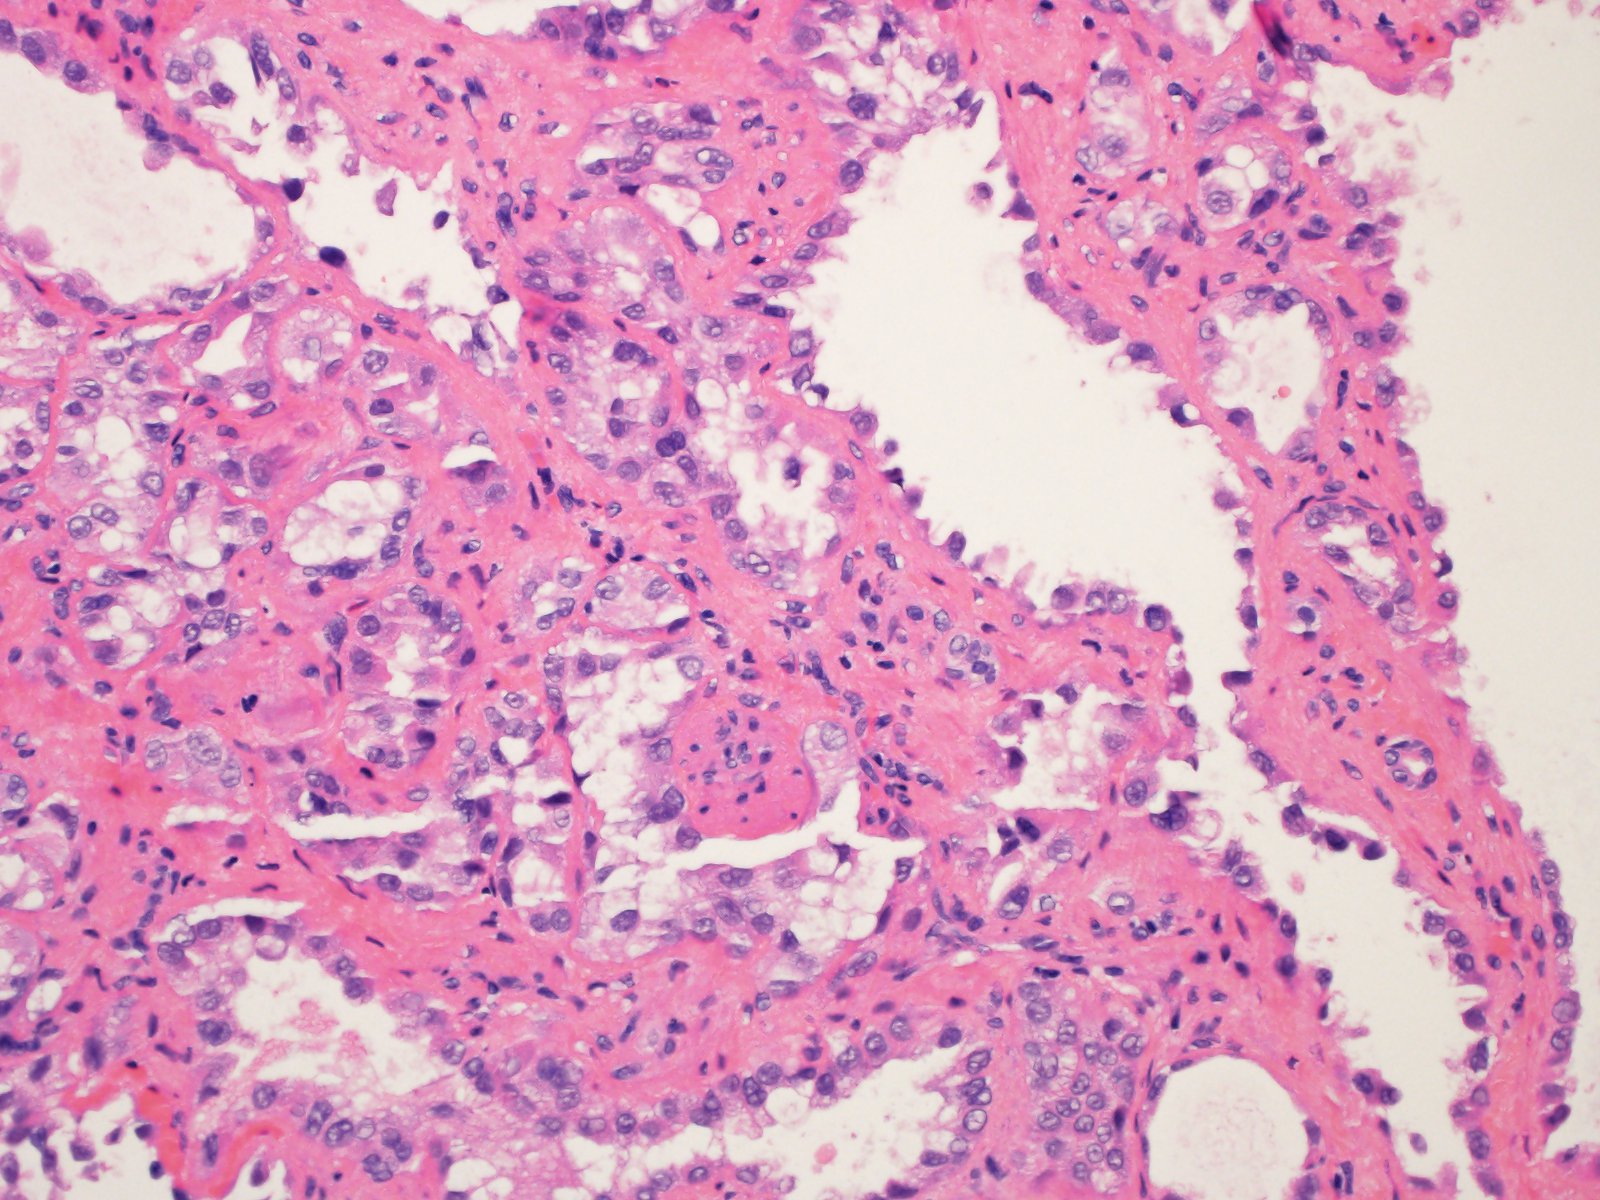

Classification of renal tumors

Case ID: 814